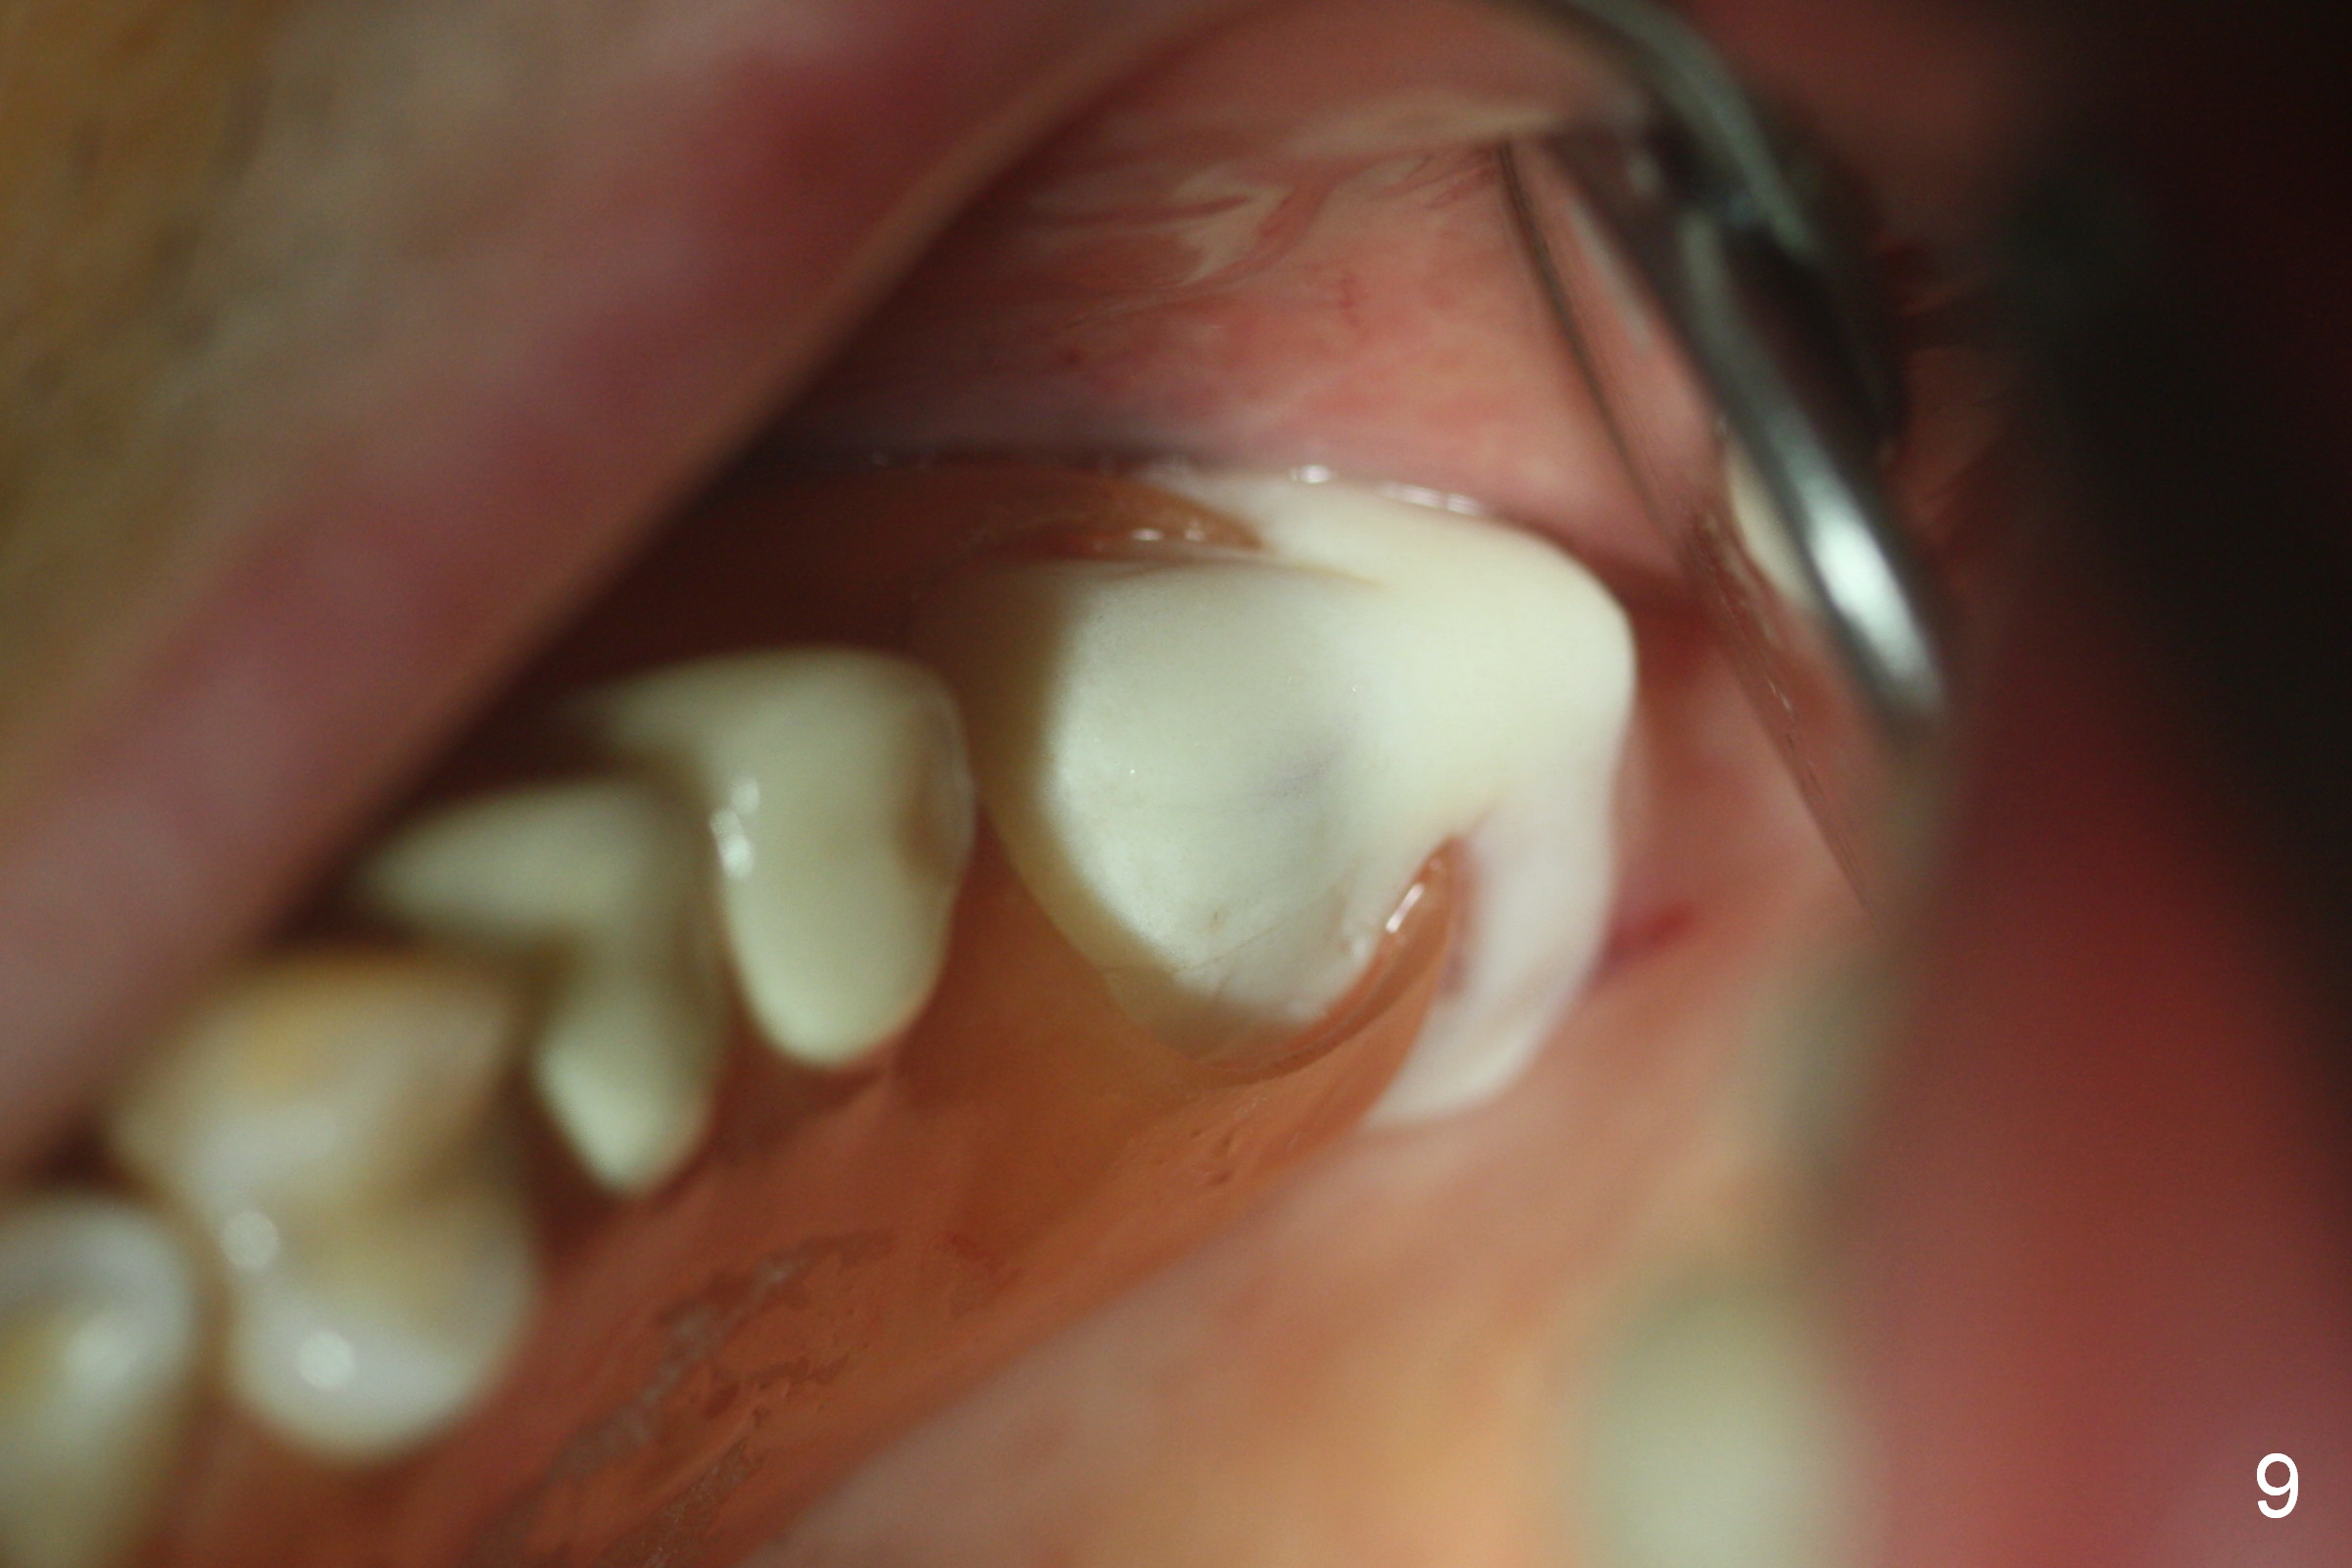

Fig.1,2 show the close relationship of the upper flipper and the residual roots at #15. Atraumatic extraction using periotomes and surgical sectioning still results in perforation of the mesiobuccal socket (Fig.3 >). The distobuccal one is shallow, while the septum is small. It appears that the palatal (Fig.3 P) socket is the most ideal recipient site for the immediate implant and is expanded with Magic Osteotomes until 4.3 mm (Fig.4,5) with the coronal end pushed as buccal as possible. After placing allograft for sinus lift (Fig.6 >), a 5x11 mm IBS implant is placed with insertion torque ~ 50 Ncm. A 6x4(3) mm pair abutment is placed, followed by bone graft in the remaining sockets (Fig.6 *) and by Osteogen plug (Fig.7 *). Finally the socket is sealed by applying acrylic over the abutment (Fig.8). While the acrylic is setting, the flipper is seated and excess acrylic is removed and pushed away from the flipper (Fig.9). Advise the patient not to wear the flipper. If it is being worn, there will be minimal contact between the flipper and the immediate provisional.